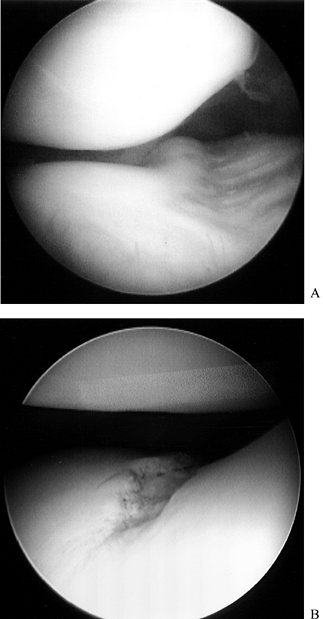

meniscus and the articular cartilage surfaces (Fig. 84.25; see also COLOR FIG. 84.25).

Figure 84.25. (See COLOR FIG. 84.25.) Arthroscopic view of the medial compartment. -

compartment. Probe the meniscus and articular cartilage surfaces (Fig. 84.26; see also COLOR FIG. 84.26).

Figure 84.26. (See COLOR FIG. 84.26.) Arthroscopic view of the lateral compartment. -

Figure 84.27. Arthroscopic view of the patellofemoral joint from the (A) superolateral portal and (B) inferolateral portal, demonstrating an injury to the articular cartilage of the trochlear groove.